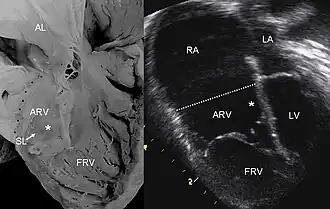

| Pathological specimen and ultrasound image of a heart with Ebstein anomaly. Abbreviations: RA: Right atrium; ARV: Atrialized right ventricle; FRV: Functional right ventricle; AL: Anterior leaflet; SL: Septal leaflet; LA: Left atrium; LV: Left ventricle; asterisk: grade II tethering of the tricuspid septal leaflet. | |